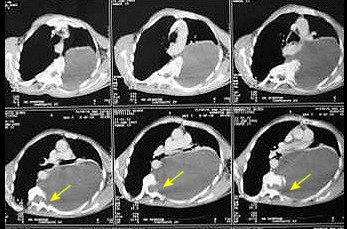

TCtorax NET OKO estudo IFCT-0302 não demonstrou diferença na sobrevida global entre pacientes com câncer de pulmão não pequenas células completamente ressecadas que receberam tomografia computadorizada (TC) como parte de seu seguimento e aqueles que não realizaram o exame. Os achados serão apresentados no Congresso ESMO 2017, que acontece entre os dias 8 e 12 de setembro, em Madri, e sugerem que as tomografias computadorizadas regulares podem não ser necessárias1.